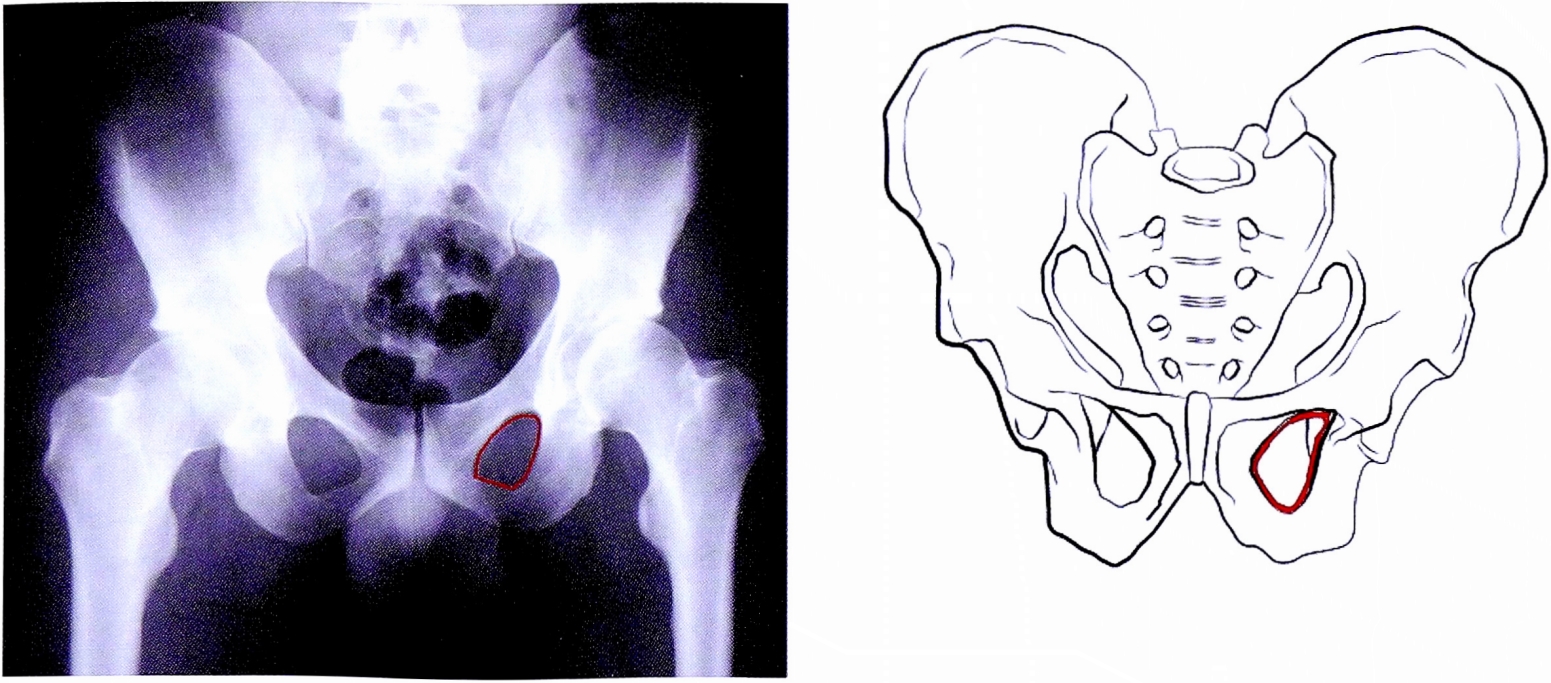

- Контуры запирательного отверстия. Нарушение непрерывности контура запирательного отверстия является признаком перелома, плоскость которого проходит через запирательное отверстие (рис. 7). Может служить диагностическим признаком повреждения одной из колонн вертлужной впадины.

Рис. 7. Непрерывный контур запирательного отверстия на рентгенограмме и на схематическом изображении таза.

Fig. 7. Intact obturatot foramen on AP pelvic X-ray and on schematic pelvis.